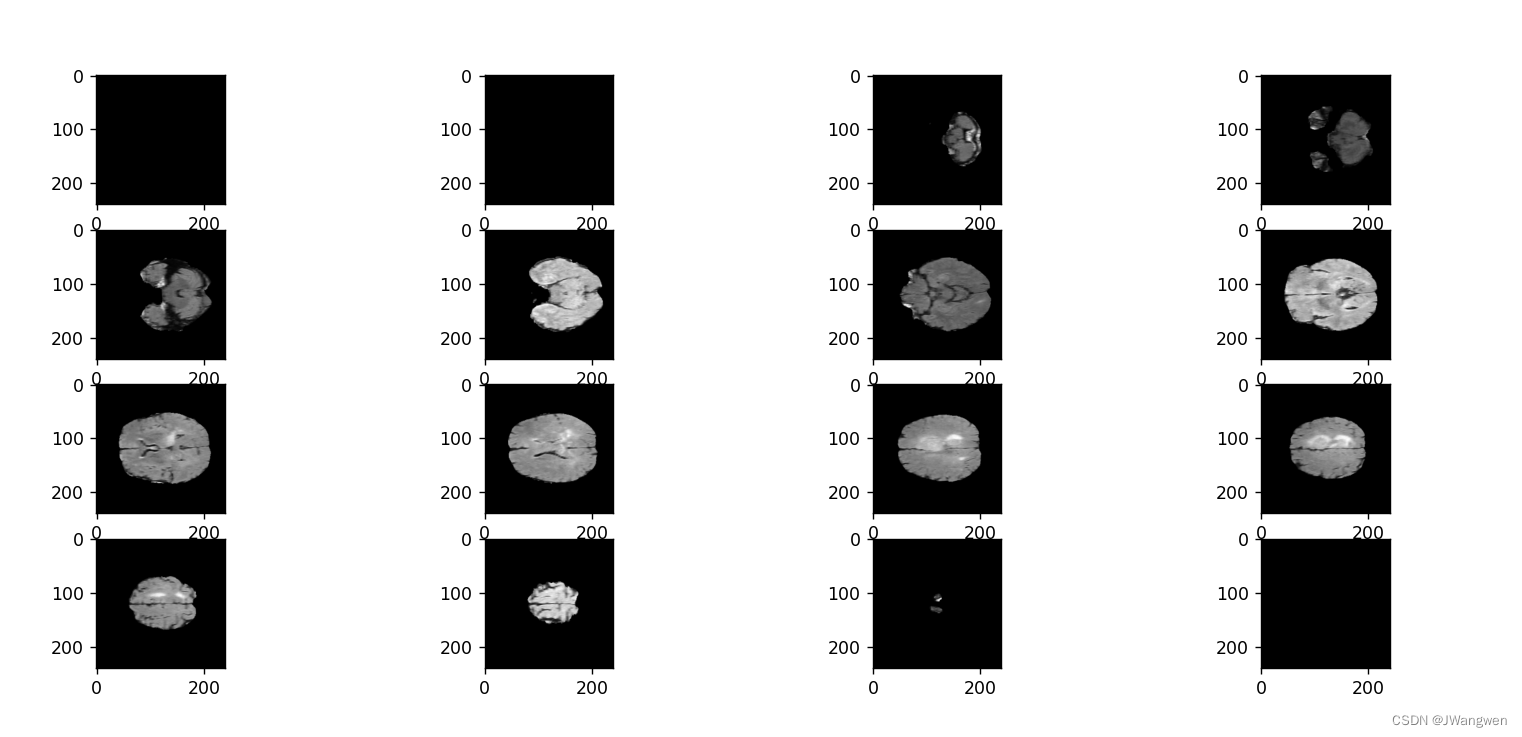

num = 1

for i in range(0,queue,10):

img_arr = img.dataobj[:,:,i]

plt.subplot(5,4,num)

plt.imshow(img_arr,cmap='gray')

num +=1

plt.show()

显示图片如下:(如果是黑色,鼠标拖动一下图片或者动一下滚轮,可能是坐标在原点)

两种方式好像第二种会显示的的是3D的,更多态化一点,光是看一下数据长什么样子的话,两种方式都能用